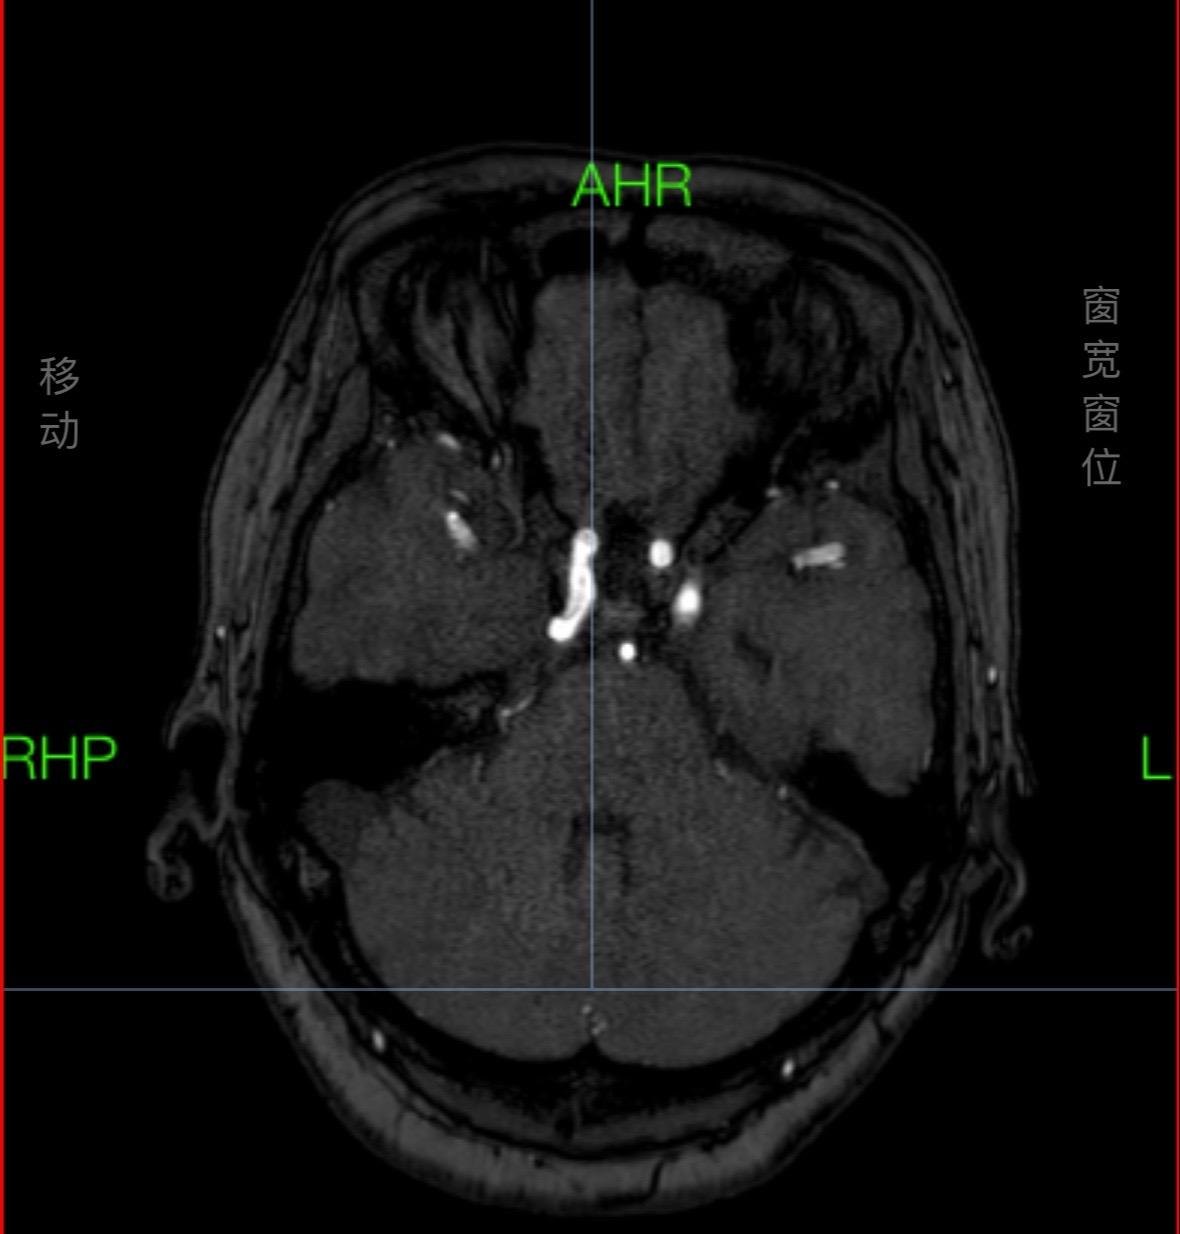

疼痛难忍。碰上这么一条“大蛇”(白色-椎基底动脉延长扩张)导致三叉神经痛,疼痛难忍,开颅风险较高,今日球囊手术顺利解决疼痛!